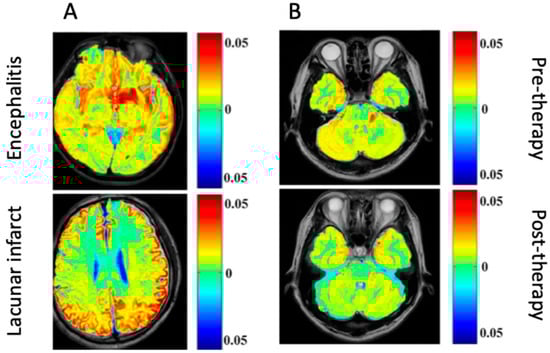

In particular, CEST has significant diagnostic potential in differentiating infective pathogenesis in the CNS from other lesions (e.g., ischemic, neoplastic). The bacCEST study [45] was able to differentiate brain abscesses and tumors, which is currently unreliable with conventional MRI techniques. Still, a statistically significant difference between the abscess and tumor signal was recorded using different B1 values (1 μT and 3 μT for brain abscess and tumor, respectively. This relationship was preserved when tested with two different tumor models in rats (specimens were injected with F98 or 9 L glioma cell lines). The gluCEST signal has also successfully distinguished between encephalitis and ischemic lesions, where glutamate concentrations are found to be decreased in lacunar infarction regions but increased in encephalitis lesions [46].

A few studies have been published regarding diagnostic investigation using gluCEST to image the destruction of the blood–brain barrier by brain abscess in SD rat specimens [4]. This preliminary study showed that gluCEST may diagnose abscesses more reliably and at a higher resolution than MRS [4]. Another study explored the use of gluCEST imaging in vivo in rats and humans to diagnose encephalitis [46]. In model rats, glutamate concentrations were significantly associated with the inflammation caused by S. aureus-induced encephalitis lesions; furthermore, the gluCEST signal increased throughout the infection. This suggests that further studies could investigate how changes in glutamate concentrations could be used to monitor encephalitis development throughout the infection [46]. Another study used gluCEST imaging to examine the detection of early changes occurring in sepsis-associated encephalopathy (SAE), a severe systemic infection complication affecting the CNS [47]. Unlike the use of conventional MRI, combining gluCEST with diffusion kurtosis imaging (DKI) could detect early abnormalities in diseased rat cohorts [47]. Lastly, another group investigated the glutamate signal changes during SAE within the hippocampus in SD rats using gluCEST [48]. In this study, H1-MRS imaging was used to understand if CEST could provide high spatial resolution for quantitative brain mapping and lesion visualization in SAE. The results found that gluCEST imaging could provide sensitive data regarding changes in glutamate in the hippocampus of the rats with SAE with comparable quality to H1-MRS imaging [48].

CEST MRI can also be used to visualize the infections of the CNS over time, essentially monitoring their status and providing information on prognosis and therapeutic efficacy. In rat models, bacCEST can monitor antibiotic therapy response in brain abscesses. This visualization method was also superior to structural MRI, as the bacCEST contrast showed a change much earlier than T2WI (after 4 days instead of 10 days) (shown in Figure 2 as an illustration) [45]. Another preclinical study investigated the effects of N-acetylcysteine (NAC) treatment on SAE in SD rats [47]. The gluCEST signal was significantly higher in the SAE group than in the NAC-treated group or the controls, and the CEST distribution also differed in the SAE group. These findings suggest that the effects of treatment on the cortex could be visualized through gluCEST imaging in this disease process.

The severity of lesions in encephalitis can also be tracked over time with gluCEST during intravenous immunoglobulin therapy. The gluCEST signal in encephalitis lesion areas was significantly decreased from pre- to post-treatment in human participants, which correlated with the signal intensity changes visualized on conventional MRI imaging [46]. However, the gluCEST signal change was specific to encephalitis lesions; lacunar infarction lesions treated with the same therapy could not be adequately visualized over time with gluCEST [46].

Generally, differences in the imaging between different events in the brain could provide a wrong diagnosis. For example, the difference between encephalitis and lacunar infarction could not provide a differential picture for an accurate diagnosis. However, a clinical study demonstrated an increase in the gluCEST signal in patients with encephalitis compared to a decreased gluCEST signal in patients with lacunar infarction [46]. To validate their finding, patients with encephalitis were treated with a cocktail of immunoglobulins, which caused a decrease in the encephalitis lesions (1.34% to 5%) (Figure 2).

Figure 2. Glutamate chemical exchange saturation transfer (gluCEST) in patients. (A) Differential images comparing encephalitis and lacunar infarct. (B) Images showing encephalitis before and after immunoglobulin therapy [46] (Images obtained from an open-access article distributed under the terms of the Creative Commons Attribution License (CC BY)).